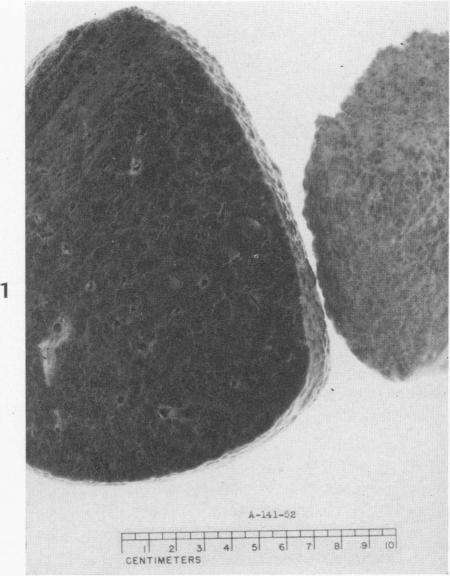

Histochemical demonstration of copper in a case of hepatolenticular degeneration.

Am J Pathol. 1955 May-Jun;31(3):545-53.

Histochemical demonstration of copper in a case of hepatolenticular degeneration.肝豆状核变性病例中铜的组织化学显示